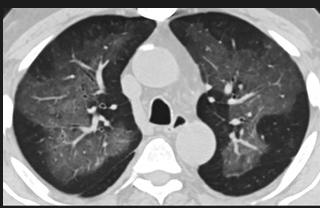

怎么“中度可疑”呢?這些專家表示,這5位患者的肺部CT都具備新冠肺炎CT的影像特征,比如肺部出現(xiàn)磨玻璃的影像,磨玻璃主要分布在雙下肺靠近外周,出現(xiàn)鋪路石征、嚴重的表現(xiàn)為雙肺彌漫性多發(fā)實變。同時,其病程轉(zhuǎn)歸和臨床特征也與新冠肺炎相似。

以下面這4張圖涉及的這個美國“電子煙”病人為例,專家不是僅僅通過一張影片做判斷的,而是通過這4張涵蓋了這名病例肺部多天變化情況的影片進行的研判,認為該病例的病程進展跟新冠更為相似。